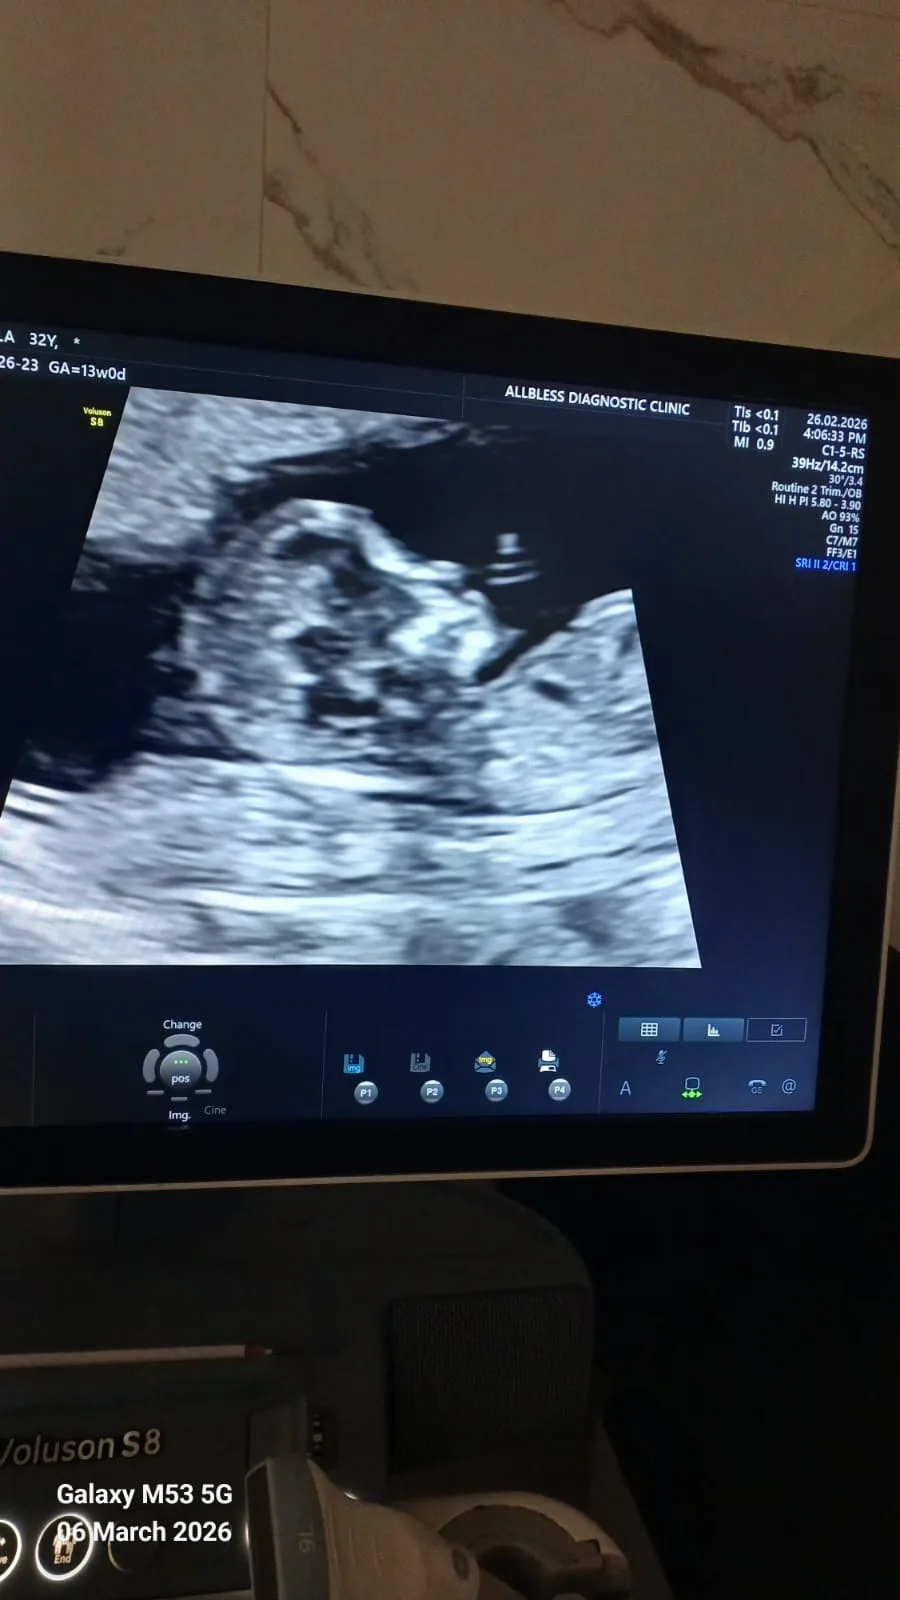

• NT Scan (First Trimester Scan) – Screens for certain chromosomal abnormalities.

Advanced ultrasound and specialized pregnancy scans are guided by 13+ years of clinical acumen and precision.

Dr. Shehzia Lakhani is a Mumbai-born Senior Radiologist and Sonologist dedicated to the highest standards of diagnostic accuracy. Her academic journey began at the prestigious TN Medical College & Nair Hospital, followed by a specialized DMRE from Bhatia Hospital. With over 13 years of hands-on experience across Mumbai’s premier medical institutions—including Nanavati, Saifee, and Allbless—she has developed a profound clinical acumen that goes beyond standard reporting. Dr. Shehzia is recognized for her approachable patient care and her ability to provide doctors with a definitive diagnostic roadmap for complex cases.